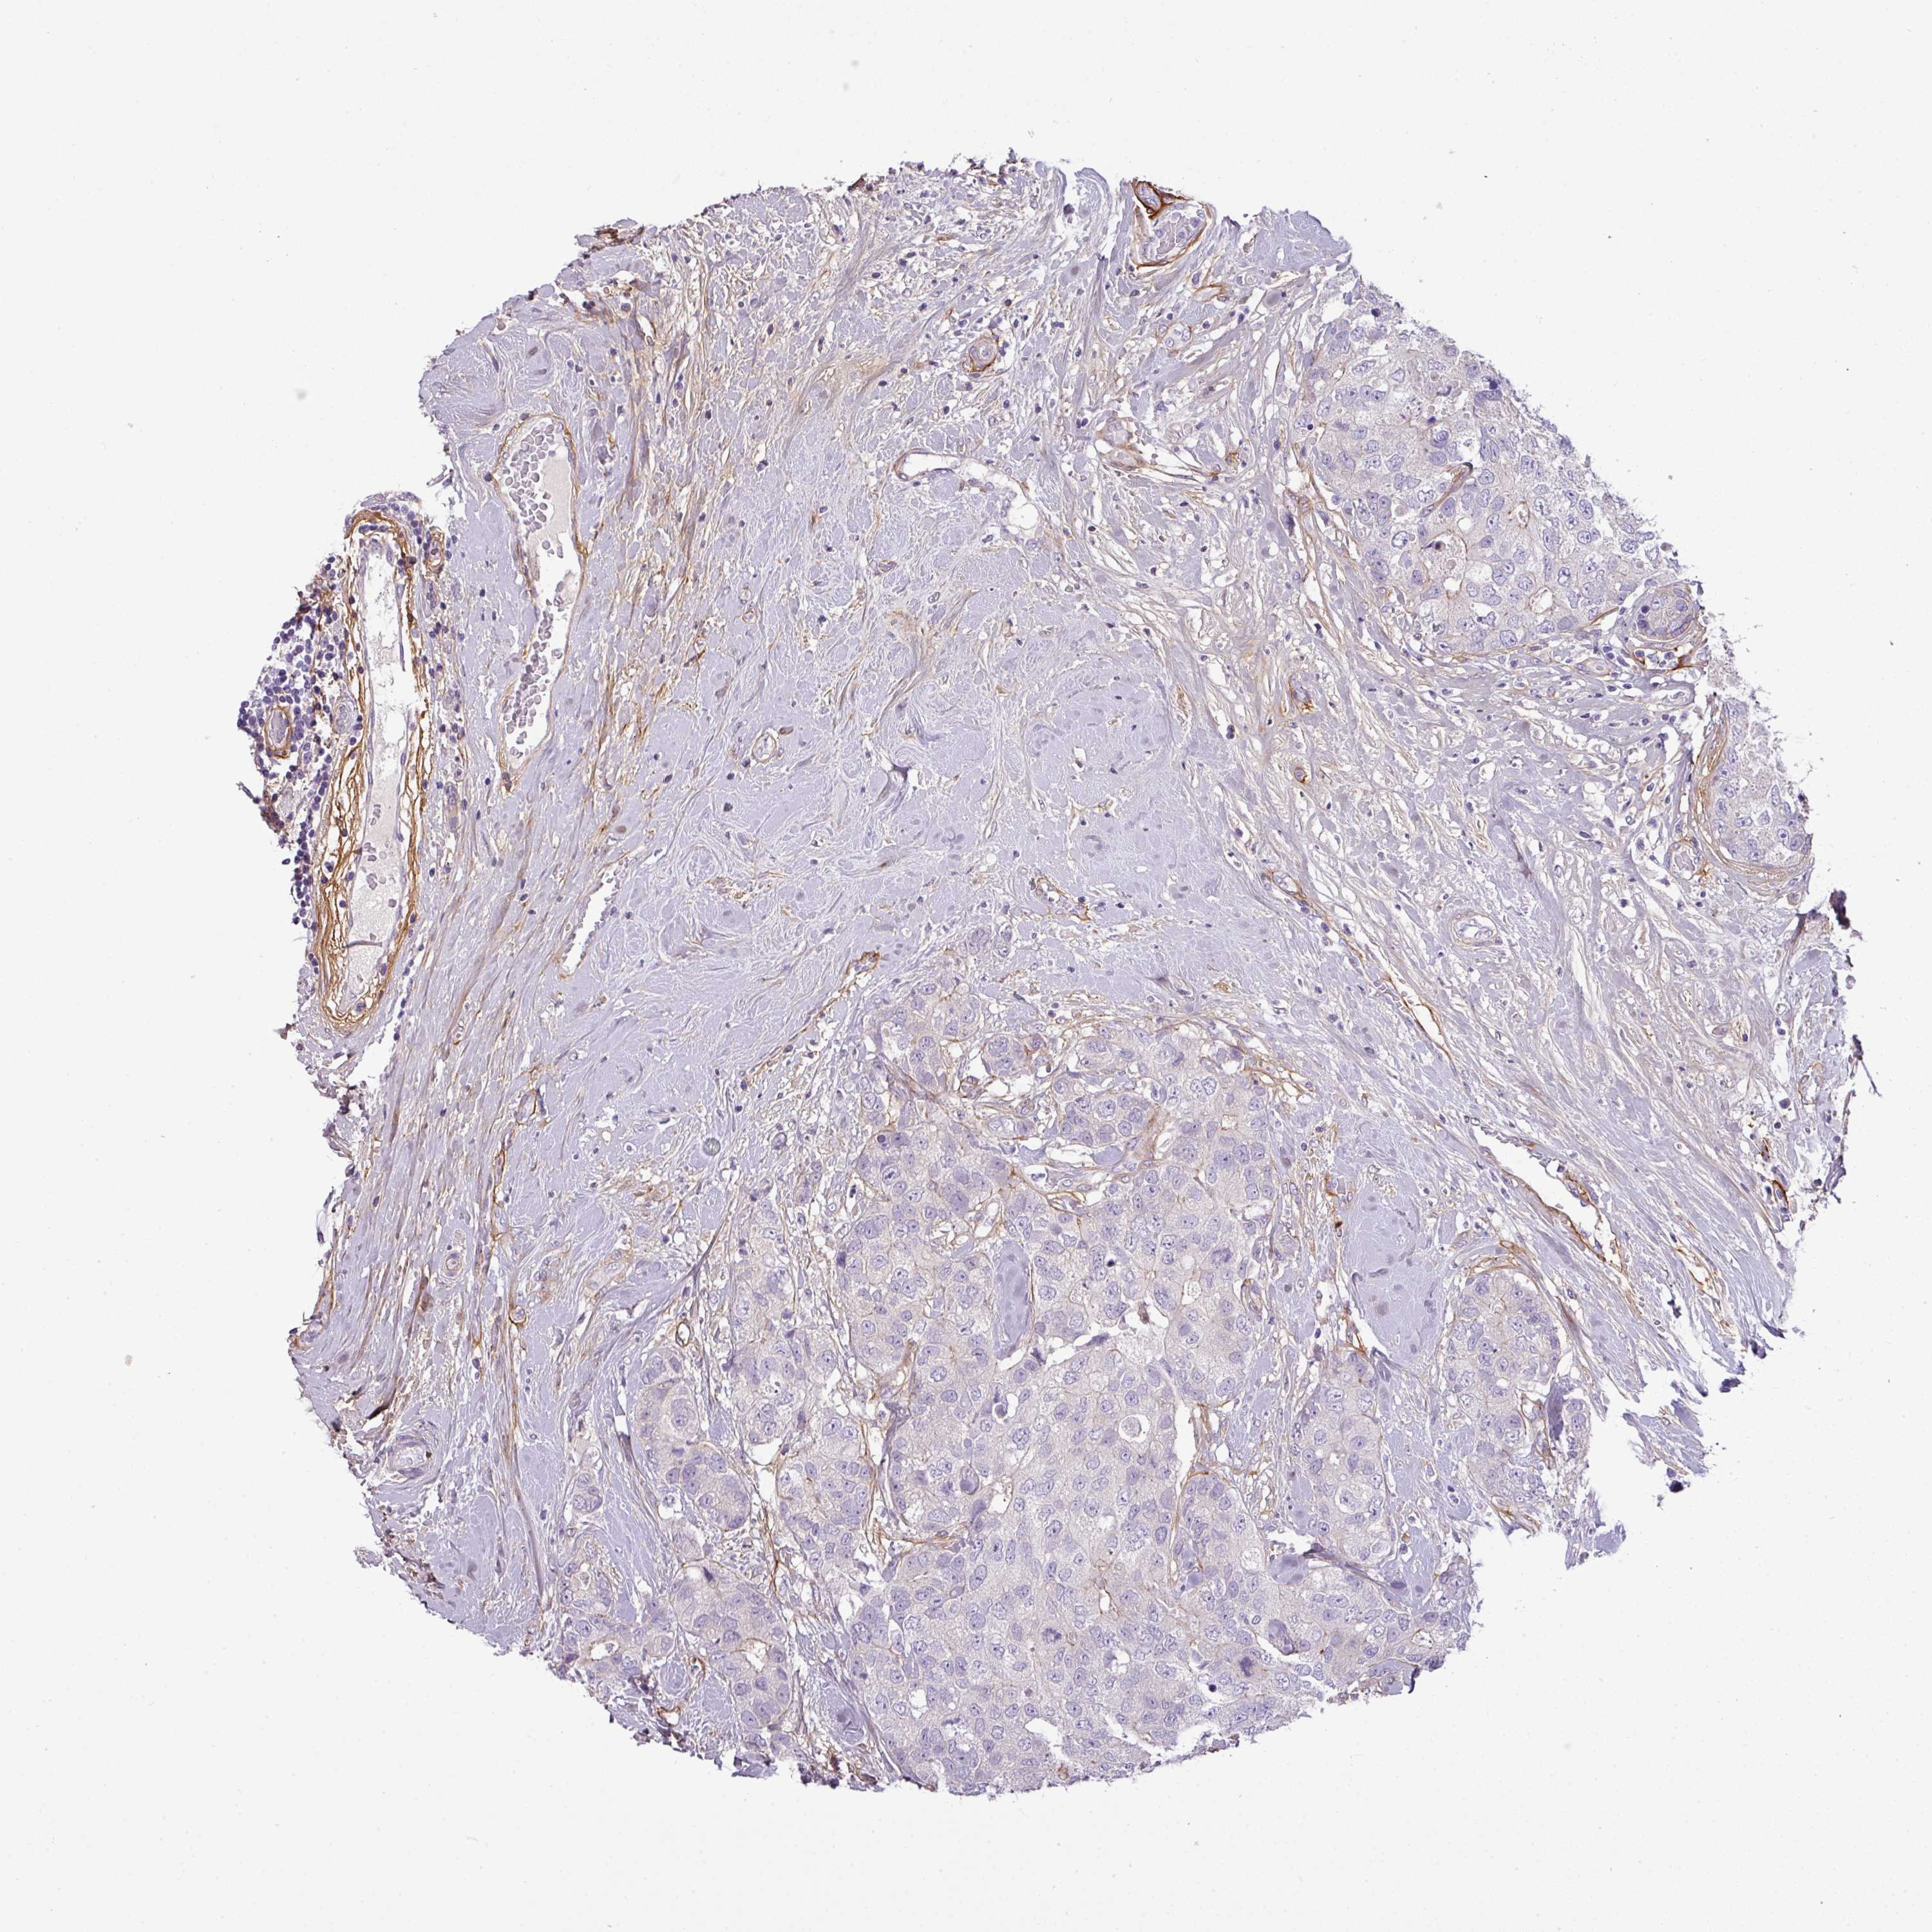

CANCER BREAST CANCER Show tissue menu

BRCA TCGA BRCA VALIDATION PROTEIN EXPRESSION

Breast cancer

Human cancer

Breast invasive carcinoma

PARD6G is not prognostic in Breast Invasive Carcinoma (TCGA)